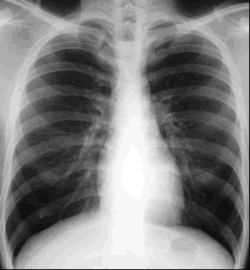

They found that 3 patients -- including 1 who was HIV positive -- experienced

short-term favorable outcomes. Sputum culture negativity occurred after

8, 11, and 20 weeks. Clinical status improved and lung lesions visible

by X-rays decreased. All 3 were still on treatment at the time of the